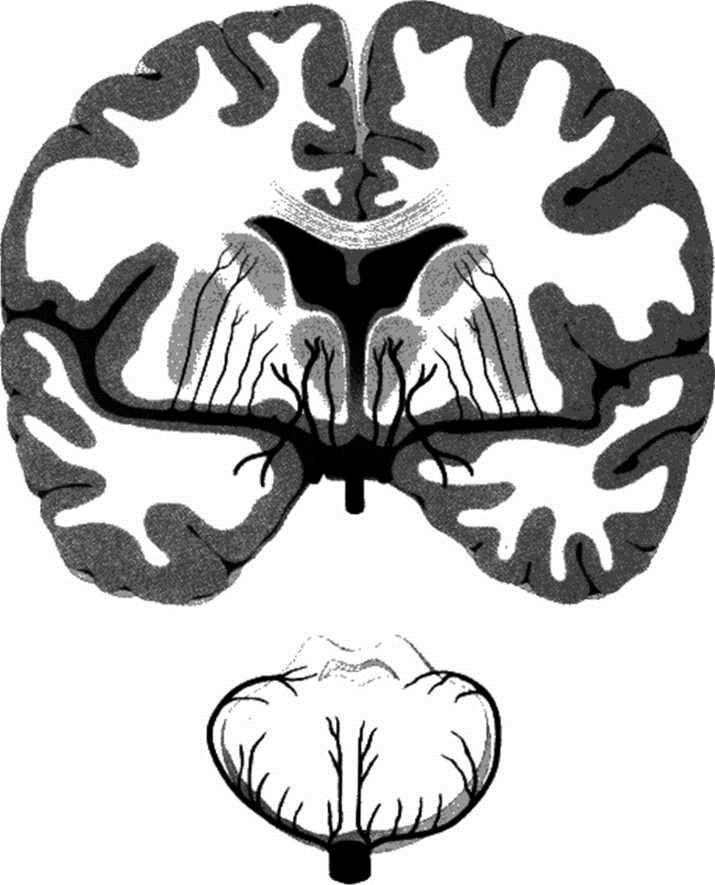

图2 大脑半球冠状面显示大脑中动脉主干及其分支——豆纹动脉

由高血压引起的脂质透明样变性和中膜过度增生主要累及:①大脑中动脉的豆纹动脉穿通支(图2);②大脑前动脉的穿支,通常指Heubner动脉(图3和图4);③前交通动脉发出的穿通支(图5和图3);④大脑后动脉发出的丘脑穿通动脉和丘脑膝状体穿支(图3);⑤由基底动脉发出,到达脑桥、中脑和丘脑的旁中央穿通支。在某些情况下,母动脉粥样硬化斑块形成或穿支口微小粥样硬化斑块会堵塞穿通动脉(图6)。动脉粥样硬化性穿支闭塞的累及部位与脂质透明样变性有相同之处,但同时前者还可累及较大的动脉(例如颈内动脉的分支脉络膜前动脉以及大脑后动脉发出的丘脑膝状体动脉)。

图3 基底节和丘脑的穿通动脉